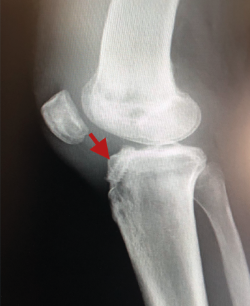

La literatura ha identificado diferentes grupos de riesgo altamente expuestos a un fracaso de la cirugía del LCA. Pacientes hiperlaxos, mujeres jóvenes o con una alta demanda funcional (deportes de pivotaje) tienen cifras mayores de fracaso(10,12). El estudio detallado de estos casos, así como la identificación de posibles factores agravantes –pendiente tibial(13), eje mecánico varo-valgo, escotadura intercondílea estrecha(14)(Figura 4)–, pueden hacer necesario añadir gestos quirúrgicos correctores, como son la osteotomía tibial, el remodelado de la escotadura intercondílea o una plastia extraarticular de refuerzo (Figura 5).

Figura 4. Escotadura intercondílea estrecha. Forma de “catedral gótica”.

Figura 16. Túnel tibial excesivamente anterior, riesgo de pinzamiento de la plastia, flexo, extrusión meniscal o rotura de la cortical anterior tibial.

En rodillas con un recurvatum (será necesario explorar ambas rodillas previamente) puede ser interesante retrasar ligeramente a posterior la emergencia intraarticular del túnel tibial con la intención de minimizar el posible pinzamiento de la plastia en hiperextensión, o bien realizar un remodelado de la escotadura intercondílea. Asimismo, en las insuficiencias crónicas del LCA se observa con más frecuencia este cierre o estrechamiento de la escotadura intercondílea que puede comprometer nuestra plastia en extensión –en forma de catedral gótica (Figura 4)–. En estos casos, es necesario realizar una condiloplastia para aumentar el espacio intercondíleo –en forma de catedral románica (Figura 5)–.